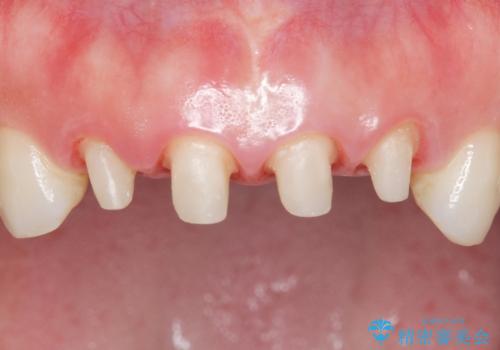

- 10年前に美容外科クリニックで前歯を治療したところ、あまりに不自然で逆にコンプレックスになってしまったことを主訴に来院された患者様です。

前歯4本の被せものは連結されており、不自然なだけではなく清掃性も悪く歯茎が著しく腫脹していました。

レントゲンを撮影したところ土台の植立も不十分であったため、土台からやりかえることにしました。

歯茎の腫脹が顕著であったため、適合の良いオーダーメイドの仮歯に変え、歯茎の状態が良くなるまで1ヶ月待ったのち型取りを行いました。